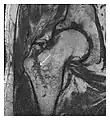

Proximal femoral fractures usually occur in osteoporotic patients, and their signs include subtle neck angulation, trabecular angulation, and subcapital impaction line. A frog-leg lateral view may be helpful if the greater trochanter is short enough. However, positioning can be difficult because of hip pain. In patients with strong suspicion of proximal femoral fracture and negative radiographs, MRI limited to coronal T1 W images and scintigraphy can be highly valuable (Figures 13 and 14). Such an option, with limited examination time, is cost-effective and allows reliable exclusion or confirmation of the diagnosis, preventing an unnecessary stay at the hospital or delayed treatment. Moreover, MRI helps to detect soft tissue abnormalities which are more frequently seen in femoral, acetabular, and pubic injuries than sacral lesions. Concomitant fractures are also frequently seen in typical pelvic sites.[1]

a

b

Figure 13: Partial osseous avulsion of the gluteal muscles at the greater trochanter in a 59-year-old man who presented with the right hip pain without a history of trauma. Lauenstein view and anteroposterior and radiographs (not shown) did not show an obvious fracture line or disruption of bony contours in the acetabulum or the right femoral neck. (a) Coronal T1-weighted MRI displays an incomplete fracture line extending partially from the greater trochanter (arrow). (b) Coronal short tau inversion recovery MRI shows heterogeneous hyperintensity in the same region (arrow) as well as hyperintensity within the gluteus medius and minimus muscles (arrowheads) consistent with tissue edema and hematoma.[1]

Figure 14: Subcapital insufficiency fracture in a 55-year-old man with a left hip pain without a history of trauma. Anteroposterior and Lauenstein view radiographs centered on the left hip do not show an obvious fracture line, but mild acetabular osteophytosis was noted consistent with hip osteoarthritis (not shown). (a) Coronal T1-weighted MRI shows a linear low-signal band through the femoral neck corresponding to a fracture line (arrowheads). (b) Bone scintigraphy shows focal uptake (arrow) corresponding to the fracture.[1]